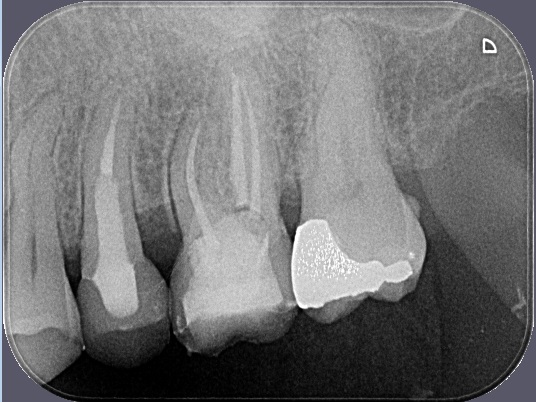

Porovnání průměrného ošetření způsobem plně hrazeným ze zdravotního pojištění (obrázek vlevo) a ošetření způsobem nadstandardním (obrázek téhož zubu po přeléčení vpravo) mohou přinést rentgenologické snímky níže.